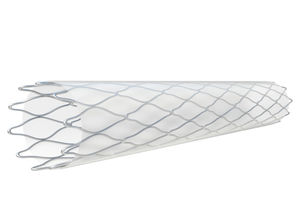

周围神经支架

... 我们对 Zilver PTX 以及库克医疗的每一件产品的使命都是努力改善患者的生活。我们已经发布了有关 Zilver PTX 的大量数据,该设备持续为众多患者带来益处。 只有 Zilver PTX 将抗增生药物紫杉醇与无聚合物药物输送和血管支持结合在一起,与经皮腔内血管成形术 (PTA) 和 Zilver 裸金属支架相比,显示出更优越的 5 年疗效。 ...

... Easy Flype是一种专用的自扩张支架,采用混合细胞设计,最大限度地提高了SFA的灵活性和适应性。 主要特点。 - 生物诱导剂表面涂层 - 有效地平衡了灵活性(用于最佳的顺应性)和径向力(用于高度钙化的血管),长度可达150mm - 单手递送系统 - 支架直径 mm: 6mm, 7mm, 8mm - 支架长度毫米:20毫米,40毫米,60毫米,80毫米,100毫米,120毫米,150毫米 - 导管长度 cm: 85cm, 135cm 更多信息请参考Alvimedica网站 生物诱导剂表面涂层实现了公认的生物和血液相容性,加速了支架的覆盖,减少了血栓形成,并对重金属离子的释放进行密封。 有效地平衡了柔韧性(用于最佳的适应性)和径向力(用于高度钙化的血管),长度可达150mm。 独特的单手递送系统提供了支架释放时的卓越轨迹和高精确度 ...

... 自膨化镍钛合金支架系统 "在单手操作系统中具有无可比拟的灵活性" 优化了灵活性和可推性与径向强度和抗扭性之间的平衡。 符合人体工程学的手柄确保了在目标病变部位的单手、准确和可控部署。 病变部位。 支架设计 由镍钛合金(Nitinol)构成 单手输送系统 双向的 支架厚度小,对血流的干扰最小 最佳的支架与管壁贴合 稳定的径向力,使血管适应性更好 扩张时支架缩短不明显 8个钽不透光标记(支架两端各4个),提供良好的可视性 输送装置 低矮的6F轴型,确保提高输送能力和病人舒适度 放射性不透光的编织护套有5个区域,具有可推性、可追踪性、灵活性、支架保护和稳定功能 可控的单手递送,无 ...

... S.M.A.R.T. CONTROL™ 支架的设计提供了具有最佳管壁贴合度的粉碎型可回收血管内支架,在保持灵活性的同时提供高桡侧阻力支持,可治疗髂骨和股骨病变*。 产品描述 输送系统长度:80 和 120 厘米 推荐导丝:0.035 英寸 S.M.A.R.T. CONTROL 支架的 36 支 6 桥结构可提供最佳的管壁定位。 S.M.A.R.T. CONTROL 支架的设计提供了具有最佳管壁定位的可回收血管内支架,在保持灵活性的同时,还能提供高径向阻力支持。 S.M.A.R.T. CONTROL ...

... 窦道 SuperFlex-535 支架是一种自膨胀镍钛诺支架。它采用开孔设计,具有更高的灵活性。 应用系统与 5F 导入鞘兼容。其长度为 75 厘米和 120 厘米。它是一种线外回拉系统,与 0.035 英寸导丝兼容。 该应用设备的一个突出特点是无尖端设计。由于省去了内部导管,因此在移除应用装置时可降低支架卡住的风险。 特点 无尖端内部导管设计,简化了取出应用装置的过程 久经考验的血管支架系统 无蒂设计 降低了应用装置在回缩过程中被支架卡住的风险。 ...

... 外周血管自膨胀支架系统 是一种具有高度耐久性和强度的灵活的镍钛合金支架,引入了一个直观的输送系统。 的特点。 钽标记,具有良好的辐射性 单手操作的输送导管 非凡的波浪设计,具有极大的灵活性和最佳的临床表现 工作长度为80厘米和120厘米,通过0.035英寸的导线引导 通过灵活的连接器具有出色的抗弯曲、抗压缩和抗扭转能力 ...

... ATLAS是一种外周自扩张支架系统,由一个OTW输送导管和一个预装的镍钛合金支架组成。ATLAS用于治疗髂动脉或股腘动脉的狭窄或闭塞病变,以建立和维持通畅性。ATLAS自扩张支架适用于经皮血管内植入,适用于动脉粥样硬化、辐射引起的和创伤后引起的血管狭窄的患者,具有血流动力学意义,并在其他形式的治疗中难以治愈。 它们适用于以下情况。 PTA手术效果不理想(残留的狭窄)。 血管内膜分层。 血管壁弹性紊乱和来自外部的压力。 复发性狭窄 ATLAS支架很容易适应动脉壁的形状,并且在部署后不会自行移位。支架的弹性和输送系统的灵活性使ATLAS甚至可以在迂回的血管中使用。 ATLAS自膨胀外周支架系统旨在改善管腔直径,以治疗长度不超过180毫米的原生股浅动脉和/或腘窝近端动脉的症状性新生或再狭窄病变,参考血管直径范围为3.5毫米至7.5毫米。 特点 由镍钛合金激光切割制成 (NiTi) ...

... BioMimics 3D® 血管支架系统 挑战。周边动脉疾病 人们的寿命越来越长,随着肥胖症、糖尿病和其他诱发因素的增加,跛行可能导致大量的组织变化,在某些情况下,可能导致截肢,甚至死亡。在技术进步、人口老龄化和合并疾病增加的推动下,周边支架市场预计到2024年将增长到20亿美元。 办法。替代技术 由于股浅动脉是一条长而相对直的血管,它在静止状态下暴露在低壁剪切应力下,容易发生动脉粥样硬化疾病,并影响血管内损伤后的愈合过程。直线支架进一步拉直了血管,扰乱了血流,形成了低壁切应力区域。 在股骨头段使用紫杉醇的药物涂层球囊和药物洗脱支架已显示出令人鼓舞的临床结果,但最近关于紫杉醇安全性的出版物将其使用置于聚光灯下,世界各地的监管机构都主张谨慎使用。 解决方案。BioMimics三维血管支架系统 Veryan公司开发了创新技术,通过采用生物仿生学原理来改善血管支架的性能;开发模仿自然界中的结构。 BioMimics ...

... 完全可生物降解的外周支架 迄今为止,REMEDY™ 是世界上唯一获得 CE 认证的可生物降解外周支架。 它可以防止由在位支架引起的再狭窄、血栓形成和免疫反应反应,并缩短抗血小板治疗的时间。 独家 通过 KMP 与 ENDOCOR 之间的特殊合作关系,我们可以为您独家提供这种独特的支架。 产品亮点 灵活性:柔性聚乳酸单丝和 "之 "字形螺旋支架结构提供了出色的灵活性。 支架材料:使用生物相容性极佳的可降解聚乳酸(PLLA);支架由具有高强度和高柔韧性的聚乳酸单丝组成。 ...

... 经过多年的建立和发展,USM Healthcare Medical Devices Factory JSC 已逐渐在越南市场的医疗器械制造领域中声名鹊起。USM Healthcare 医疗器械厂股份公司在越南市场的医疗器械制造领域已逐渐声名鹊起。USM Healthcare 已决定推出具有众多卓越功能的产品 DYLANO 支架。 DYLANO 支架适用于参考血管直径为 3.0 毫米至 11.0 毫米、符合支架植入条件的患者,旨在扩大外周动脉管腔并保持血管通畅。 应选择比参考血管直径大 0.5 ...

... FACILE 自扩张支架将高度耐用的镍钛诺支架与灵活的输送系统相结合,并且由于采用了创新的双向扭转设计,它是唯一一款可同时治疗左右腿动脉的设备。 柔韧性和强度 > 独特的波浪设计在提供灵活性的同时不影响径向强度 > 柔性连接器具有很强的抗弯曲、抗扭转和抗压缩应力能力 > 高度灵活的输送导管便于迂曲解剖结构的导航 准确性和易用性 > 带钽标记的镍钛诺支架在透视下清晰可见 > 最小的前缩短确保了准确的定位和放置 > 输送导管可确保 1:1 的准确轻松输送 多区导管 > 多区编织导管鞘具有鲜明特点 > ...